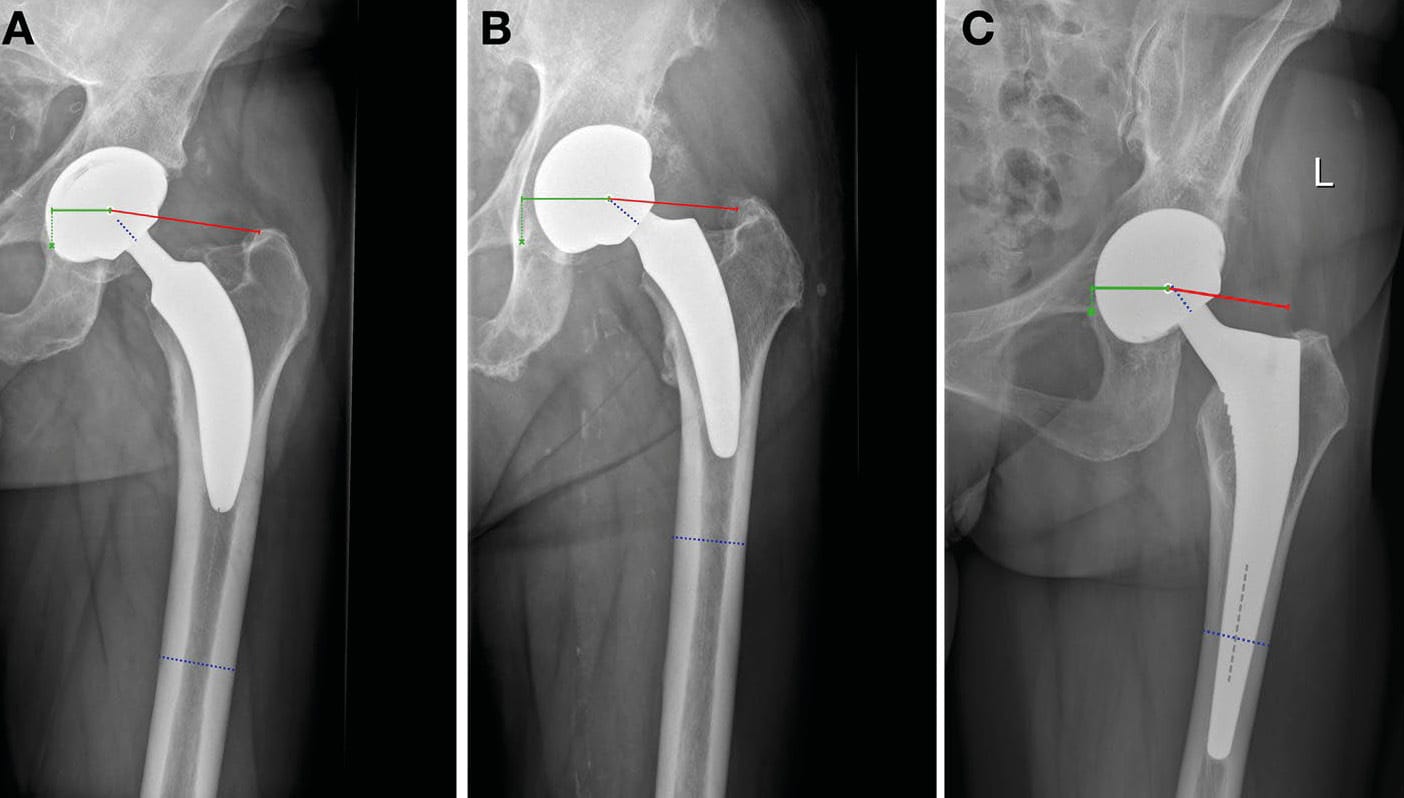

Preoperative as well as postoperative radiographic images (3 months median time from surgery to image) of the pelvis were used to perform measurements of the CCD angle, femoral offset, acetabular offset and total off-set. Radiographic measurements were carried out by two experienced observers using mediCAD® Classic Hip 2D (Hectec GmbH, Aldorf bei Landshut, Germany; Figure 2), who consulted each other in difficult cases. All radiographic images had been performed following a standard protocol, with patients standing straight, feet pointing inwards by 10°, patellae oriented frontwards, and a radio-opaque ball of 25 mm in size centred at the level of the hip joint in order to allow for image calibration in mediCAD®. Femo- ral offset was measured with a line at 90° to the femoral shaft-axis to the centre of rotation of the femoral head, and the acetabular offset with a line in parallel with the ground to the tear drop figure. The sum of femoral and acetabular offset resulted in the total offset. The CCD angle was measured using a line following the femoral neck as well as a line following the axis of the femoral shaft.